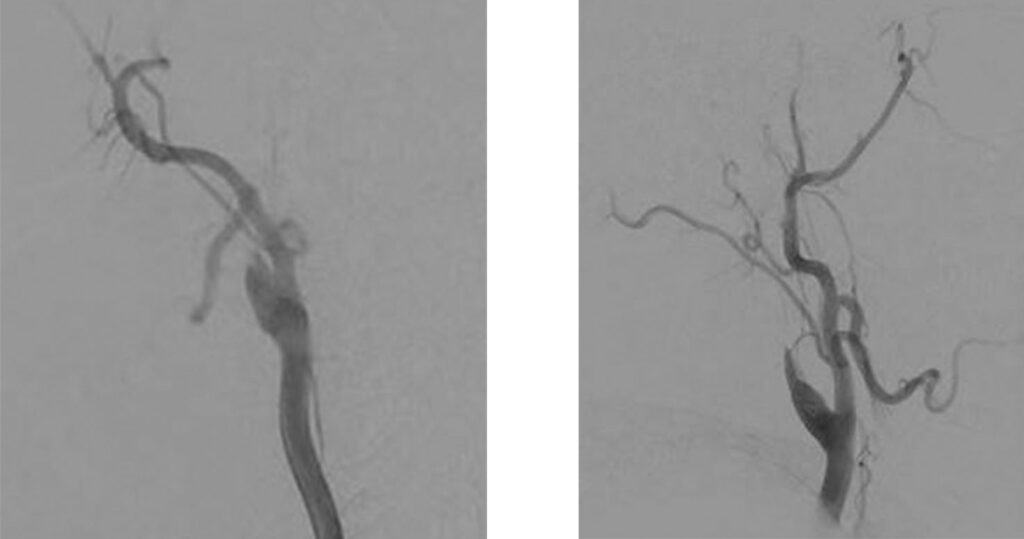

Angiographic AP and LL views showing blood flow arrest in the R-ICA after the bulb (“stump flow”) due to the occlusion of the intracranial segment of the ICA

AP and LL images from the roadmap during the navigation across the occluded segment.

Selective injection into the right M1 segment to confirm the correct distal position of the microcatheter.